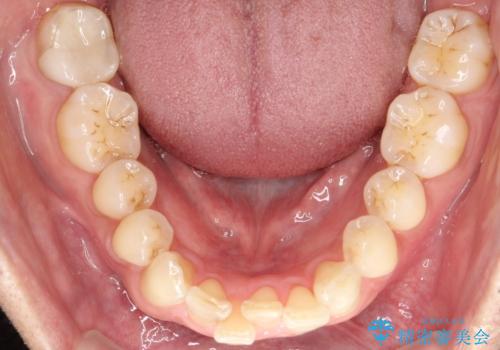

【インザライン】前歯の凸凹を治したい

- 前歯の凸凹を主訴に来院されました。

下顎位が右方に変異しており、外科矯正も提案しましたが患者様は希望されず、インビザラインにて治療を完了しております。

叢生のスペースを確保するために、臼歯部の遠心移動を行っています。

今回の治療計画は上顎の正中を顔と揃えることを優先しています。